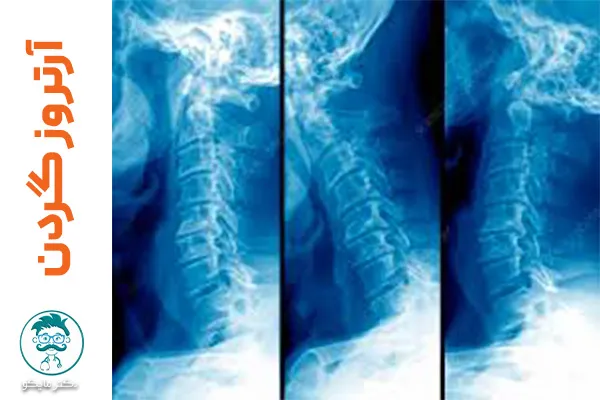

آرتروز گردن می تواند باعث درد و سفتی گردن شود که معمولا به خاطر ساییده شدن و یا پارگی دیسک های ستون فقرات اتفاق می افتد. آرتروز گردن در جوانی هم ممکن است اتفاق بیفتد اما بیشتر در افراد بالای 60 سال شایع است. البته این بیماری از آن دست مشکلاتی نیست که فقط با جراحی قابل حل باشد و راه های زیادی برای درمان علائم و درد آن وجود دارد. در این مقاله از دکتر مایکو با ما همراه باشید تا با این راه ها آشنا شویم.

آرتروز گردن چیست؟

علاوه بر سن، شرایط کاری فرد و فشار مداوم و زیاد به گردن می تواند باعث این نوع دردناک از آرتروز شود. گردن فرد وقتی دچار این مشکل می شود که دیسک های ستون فقرات او فرسوده و یا خشک شده باشد. گاهی درد آرتروز گردن پخش می شود و کتف، دست راست و یا چپ هم درگیر می کند. بنابراین لازم است حتما به موقع برای تشخیص و درمان این بیماری اقدام کنید.